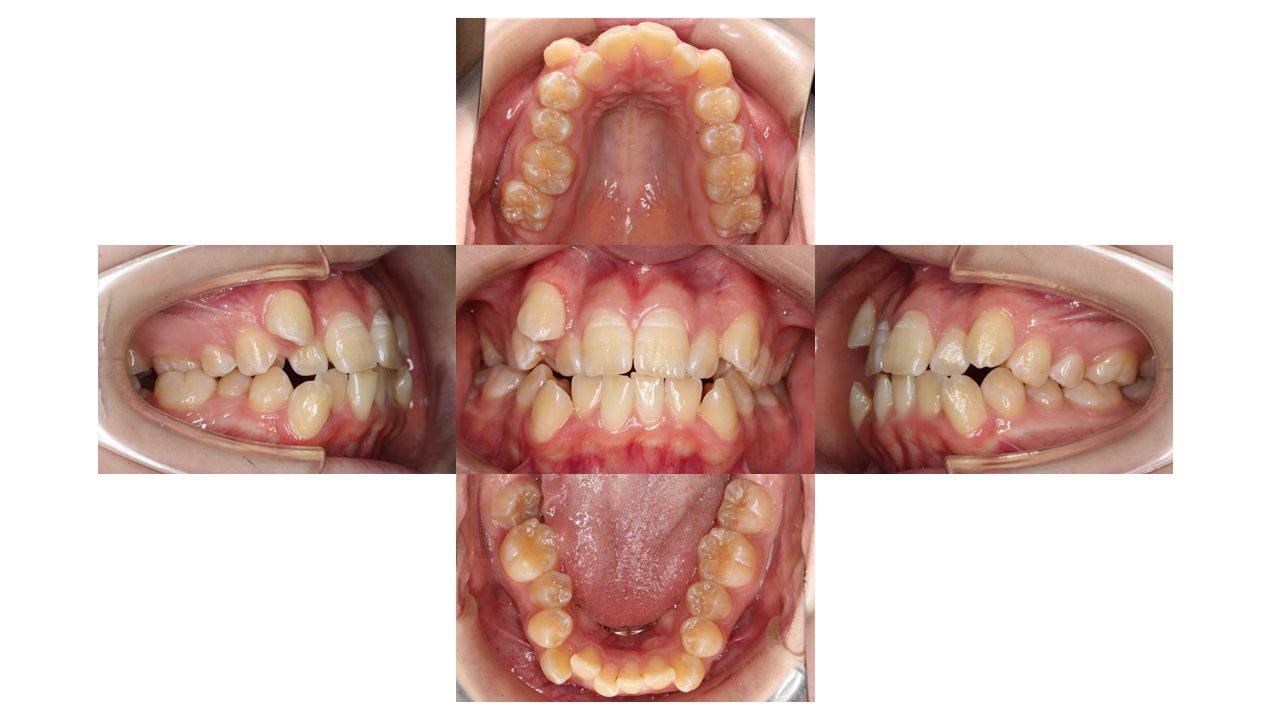

初診時の口腔内の状態です。

前歯の凸凹、特に八重歯にお悩みでご来院されました。